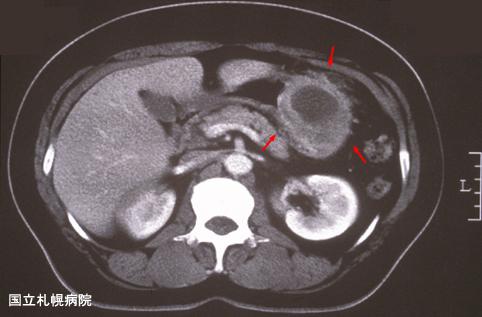

形态上表现为胃粘膜下肿瘤,术前诊断比较困难的一例炎性肿瘤

[ Image ID:3743 ]

胃(部位)/体部

CT

40以上